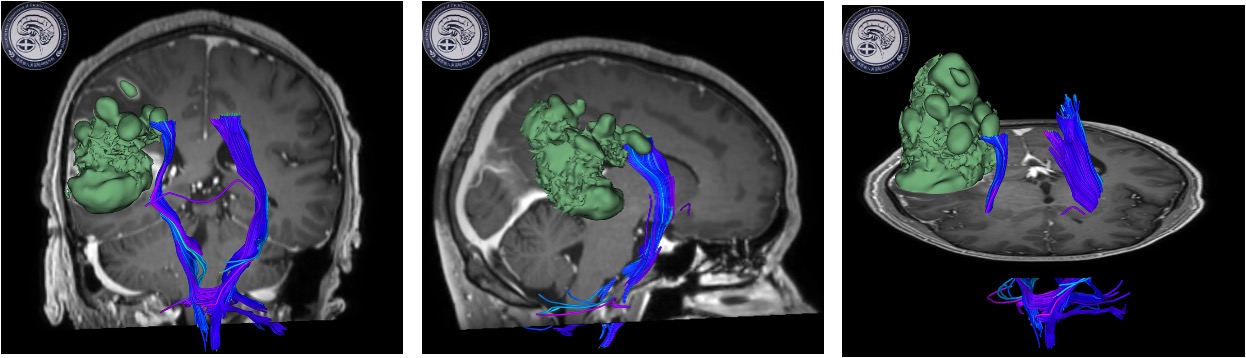

患者为成年男性,因头痛伴间断晕厥1月,在当地医院检查发现右颞顶叶多发占位病变,考虑胶质瘤。因肿瘤功能区关系密切,术后可能出现肢体运动障碍。如何做到在尽量全切肿瘤同时做好神经功能保护,对于神经外科医生来说是一种挑战。术前全科详细讨论病例制定了手术方案,决定在电生理监测下进行手术,近日由缪星宇主任医师、孟发财副主任医师、刘凯飞主治医师成功为患者实施了手术。术中在电生理运动诱发电位的监测下,结合多模态影像技术,显微镜下全切肿瘤,成功利用电生理监测技术保留运动区结构和功能,术后患者恢复顺利,病理结果确定胶质瘤诊断。

神经电生理监测是神经外科手术中监测神经功能完整性、减少神经损伤、提高手术质量所必不可少的组成部分,也是神经外科手术功能区保护的金标准。该患者采用的术中运动诱发电位监测是神经电生理监测技术之一,通过经电刺激神经或皮层,对照操作前的肌肉复合动作电位波幅和潜伏期基线,可判断神经、传导束的功能变化情况,为手术中实时监测神经功能提供有用的信息,是神经外科手术中常有监测技术之一,广泛用于颅脑和脊髓手术。在诱发电位的监测下,可以早期判断神经的位置和走形,监测神经功能变化,避免神经损伤。

通俗点说,术中神经电生理监测就像安装了GPS,哪里有神经信号传导要避开,哪里可以放心大胆的剥离,只要看到屏幕上跳动的信号,就一目了然。有了这样精准的导航,不仅能够彻底切除肿瘤,还最大程度保护了脑组织和功能。